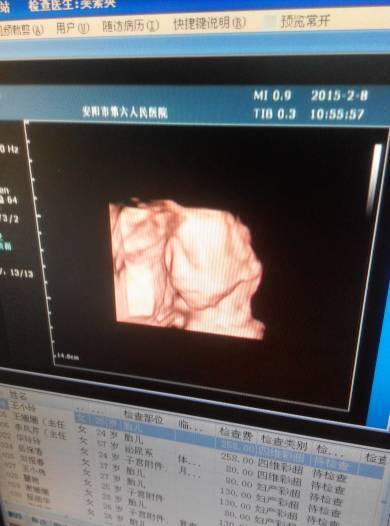

为什么我做的四维都只有胎儿的头部!看不见胳膊跟腿!做完四维之后医生说没问题!

四维就是只给头部的

你好,在做的时候医生还是会看手脚是否有问题的,可能在最后的结果中只有面部的情况,这个是没有什么问题的、